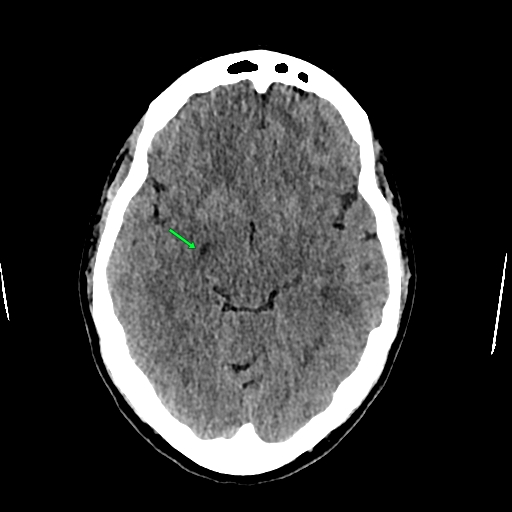

TC cerebral simple, axial. Se observa imagen ovoidea hipodensa en el sitio anatómico de la fisura coroidea derecha; hallazgo sugestivo de quiste de fisura coroidea derecha.

Paciente femenina de 29 años, quien se realiza tomografía cerebral contrastada por sintomatología de cefalea; al realizar la tomografía cerebral no se identifican alteraciones de importancia; únicamente en el sitio anatómico de la fisura coroidea derecha, se identifica imagen ovoidea, hipodensa, sugestiva de quiste de fisura coroidea derecha.